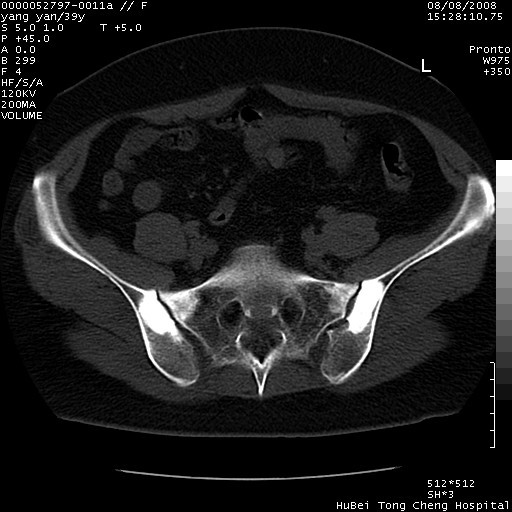

患者 女,39岁。因外伤检查,偶然发现。

典型!双侧骶髂关节致密性骨炎。

典型!病变主要累及双侧髂骨。常见于育龄期妇女。

致密性骨炎,一般不跨越关节面,可是这个骶骨关节面也有硬化。

髂骨致密性骨炎系一种以骨质硬化为特点的非特异性炎症,有高度致密的骨硬化现象,尤其以髂骨下2/3更为明显,但关节间隙则无改变。因位于骶髂关节,且该关节症状明显,故又称之为“骶髂关节致密性骨炎”。 本病90%以上为中年女性,以妊娠后期、尤其分娩后为多见,亦可见于尿路或女性附件慢性感染后,或盆腔内其他感染。此外,臀骶部的外伤亦可诱发或引起本病。  妊娠、分娩及外伤均可引起骶髂关节韧带的撕裂而易使局部的血供受阻。因此早期局部呈现充血、水肿及渗出增加等,渐而局部出现增生与变性反应,随着胶原纤维的致密化而向硬化演变;血管形成厚壁血管,易闭塞而引起髂骨耳状面处缺血和缺氧,骨质呈现硬化性改变,以致手术时局部出血较少。骶髂关节囊壁显示纤维增生、弹性降低及松动样改变。继发于盆腔内炎症者亦出现相类似的病理改变,可能系细菌内毒素作用所致。